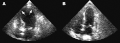

(A) Echocardiogram showing dilatation of the left ventricle in the acute phase (B) Resolution of left ventricular function on repeat echocardiogram six days later (A) Echocardiogram showing dilatation of the left ventricle in the acute phase (B) Resolution of left ventricular function on repeat echocardiogram six days later